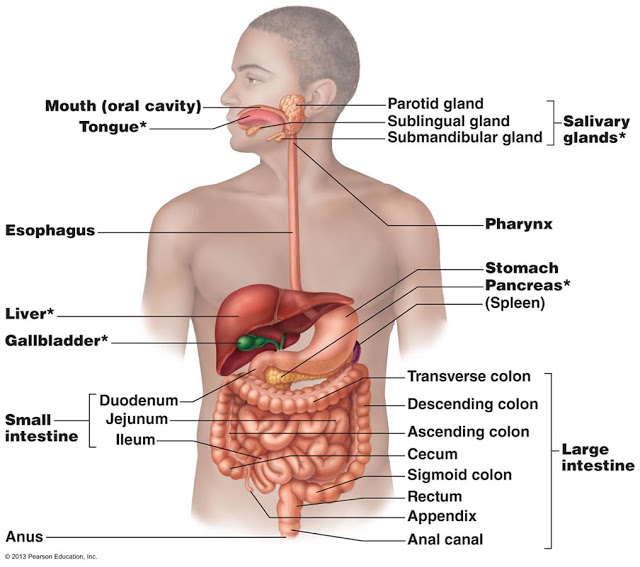

Digestion is the process by which food substances are broken down into simple and soluble form. All the parts of the body which work together to ensure digestion of food are called the digestive system.

PARTS OF THE DIGESTIVE SYSTEM

1. MOUTH:

The mouth takes in the food, the teeth chew the food, the food is mixed with saliva to soften it before it is swallowed. Enzyme in saliva called ptyalin digests carbohydrates into simple sugar. Proteins, fats and oil are not digested from the mouth, food is only masticated, mixed with saliva and swallowed.

2. GULLET:

The gullet is a long tube or passage way that connects the mouth to the stomach, it provides passage for food into the stomach but no digestion takes place in the gullet.

3. STOMACH:

The stomach is a sac-like organ that provides temporary storage for swallowed food. Carbohydrate is churned into chyme (semi fluid food), mixed with gastric juice, acidified and the bacteria in the food are killed. Proteins are also churned into chyme, and the enzyme called pepsin digests proteins into peptones. Enzyme called rennin changes fat in milk into semi solids.

4. SMALL INTESTINE:

The small intestine is a long narrow tube which is long as 8 metres. The small intestine has 3 components.

(1) Duodenum

(2) Jejunum

(3) Ileum

Carbohydrates, proteins, fats and oil acidity is neutralized. Carbohydrates and proteins are turned into semi fluid called chyme while fats and oil are emulsified (changed to droplets).

Carbohydrates are finally digested into simple sugars and are absorbed into the blood stream and circulated. Proteins are finally digested from peptones into amino acids, absorbed and circulated. Emulsified fats and oil are digested into fatty acid and glycerol, absorbed into the blood stream and circulated.

Digestion is the process by which food substances are broken down into simple and soluble form. All the parts of the body which work together to ensure digestion of food are called the digestive system.

PARTS OF THE DIGESTIVE SYSTEM

1. MOUTH:

The mouth takes in the food, the teeth chew the food, the food is mixed with saliva to soften it before it is swallowed. Enzyme in saliva called ptyalin digests carbohydrates into simple sugar. Proteins, fats and oil are not digested from the mouth, food is only masticated, mixed with saliva and swallowed.

2. GULLET:

The gullet is a long tube or passage way that connects the mouth to the stomach, it provides passage for food into the stomach but no digestion takes place in the gullet.

3. STOMACH:

The stomach is a sac-like organ that provides temporary storage for swallowed food. Carbohydrate is churned into chyme (semi fluid food), mixed with gastric juice, acidified and the bacteria in the food are killed. Proteins are also churned into chyme, and the enzyme called pepsin digests proteins into peptones. Enzyme called rennin changes fat in milk into semi solids.

4. SMALL INTESTINE:

The small intestine is a long narrow tube which is long as 8 metres. The small intestine has 3 components.

(1) Duodenum

(2) Jejunum

(3) Ileum

Carbohydrates, proteins, fats and oil acidity is neutralized. Carbohydrates and proteins are turned into semi fluid called chyme while fats and oil are emulsified (changed to droplets).

Carbohydrates are finally digested into simple sugars and are absorbed into the blood stream and circulated. Proteins are finally digested from peptones into amino acids, absorbed and circulated. Emulsified fats and oil are digested into fatty acid and glycerol, absorbed into the blood stream and circulated.